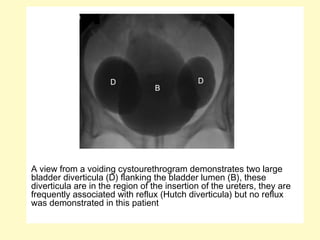

A view from a voiding cystourethrogram demonstrates two large

bladder diverticula (D) flanking the bladder lumen (B), these

diverticula are in the region of the insertion of the ureters, they are

frequently associated with reflux (Hutch diverticula) but no reflux

was demonstrated in this patient